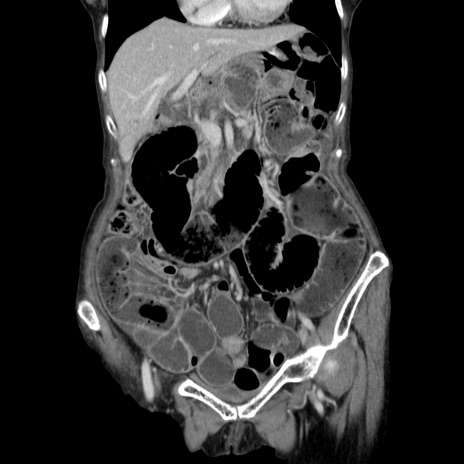

症例25(冠状断像)

【症例】80歳代女性

【主訴】胸のつかえ感

【現病歴】約9時間前に食後から胸のつかえた感じあり、嘔吐あり、来院。

【既往歴】胃癌(全摘)、胆摘、虫垂炎

【身体所見】心窩部に圧痛あり、反跳痛なし。

【データ】WBC 5700、CRP 0.05